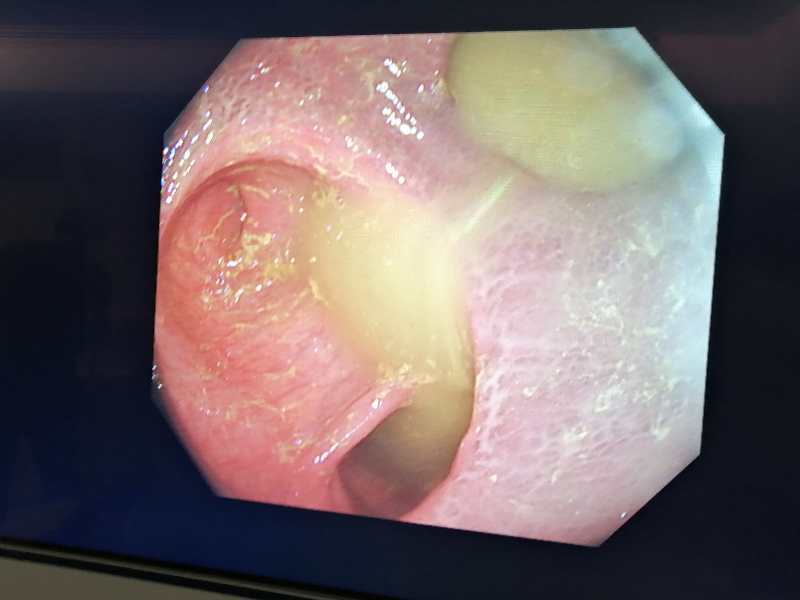

患者,女,因頑固性便秘,之前行回腸直腸吻合術(shù),病變結(jié)腸給予了保留,術(shù)后癥狀無(wú)任何改善,門(mén)診收入院后給予完善的便秘相關(guān)檢查,行結(jié)腸傳輸試驗(yàn)、排糞造影、腸鏡檢查,診斷為混合型便秘(慢傳輸型便秘,直腸前突),腸鏡可見(jiàn)第一次手術(shù)情況,見(jiàn)下圖。 故昨天在全麻下行腹腔鏡下全結(jié)腸切除術(shù)+直腸前突修補(bǔ)術(shù)

昨日?qǐng)F(tuán)隊(duì)為一例頑固性便秘術(shù)后的患者再行手術(shù),該女性患者2018年因頑固性便秘在上海某知名三甲醫(yī)院行回腸直腸吻合術(shù),術(shù)后便秘癥狀無(wú)改善,上周就診于全應(yīng)軍主任專家門(mén)診,初步評(píng)估為頑固性結(jié)腸慢傳輸便秘,此前手術(shù)僅行回直腸吻合,并沒(méi)有起到結(jié)腸曠置的效果。 收住院,行結(jié)腸傳輸試驗(yàn)、排糞造影、腸鏡檢查全面評(píng)估。結(jié)腸傳輸試驗(yàn)發(fā)現(xiàn)經(jīng)過(guò)72小時(shí)全部粒子滯留在橫結(jié)腸和降結(jié)腸,慢傳輸便秘診斷明確。排糞造影提示直腸前突25mm,出口梗阻性便秘亦存在。此患者考慮為混合型便秘。腸鏡檢查明確上次外院手術(shù)為回腸和直腸側(cè)側(cè)吻合,結(jié)腸黑病變。腸鏡距肛門(mén)20cm見(jiàn)結(jié)腸回腸吻合口。 全應(yīng)軍主任分析病情認(rèn)為回腸直腸吻合治療便秘僅適合年老體弱患者,此患者六十多歲,一般情況良好,首次手術(shù)吻合方式并不解決便秘,需要更徹底的手術(shù)。 8月14日全麻下行腹腔鏡全結(jié)腸切除術(shù)+直腸前突經(jīng)肛修補(bǔ)術(shù),手術(shù)切除全部傳輸慢的結(jié)腸,連同原手術(shù)的吻合口,徹底解決慢傳輸和出口梗阻便秘。該患者年輕的時(shí)候因血吸蟲(chóng)脾腫大做過(guò)開(kāi)腹脾臟切除術(shù),加之18年的回直腸吻合術(shù),腹腔存在比較嚴(yán)重的粘連,但手術(shù)團(tuán)隊(duì)仍然嫻熟的在腹腔鏡下完成整個(gè)手術(shù)操作。腹腔鏡微創(chuàng)手術(shù),僅僅通過(guò)肚子上幾個(gè)小孔就完成,術(shù)后患者恢復(fù)順利,今日術(shù)后第一天患者即可下床活動(dòng)。